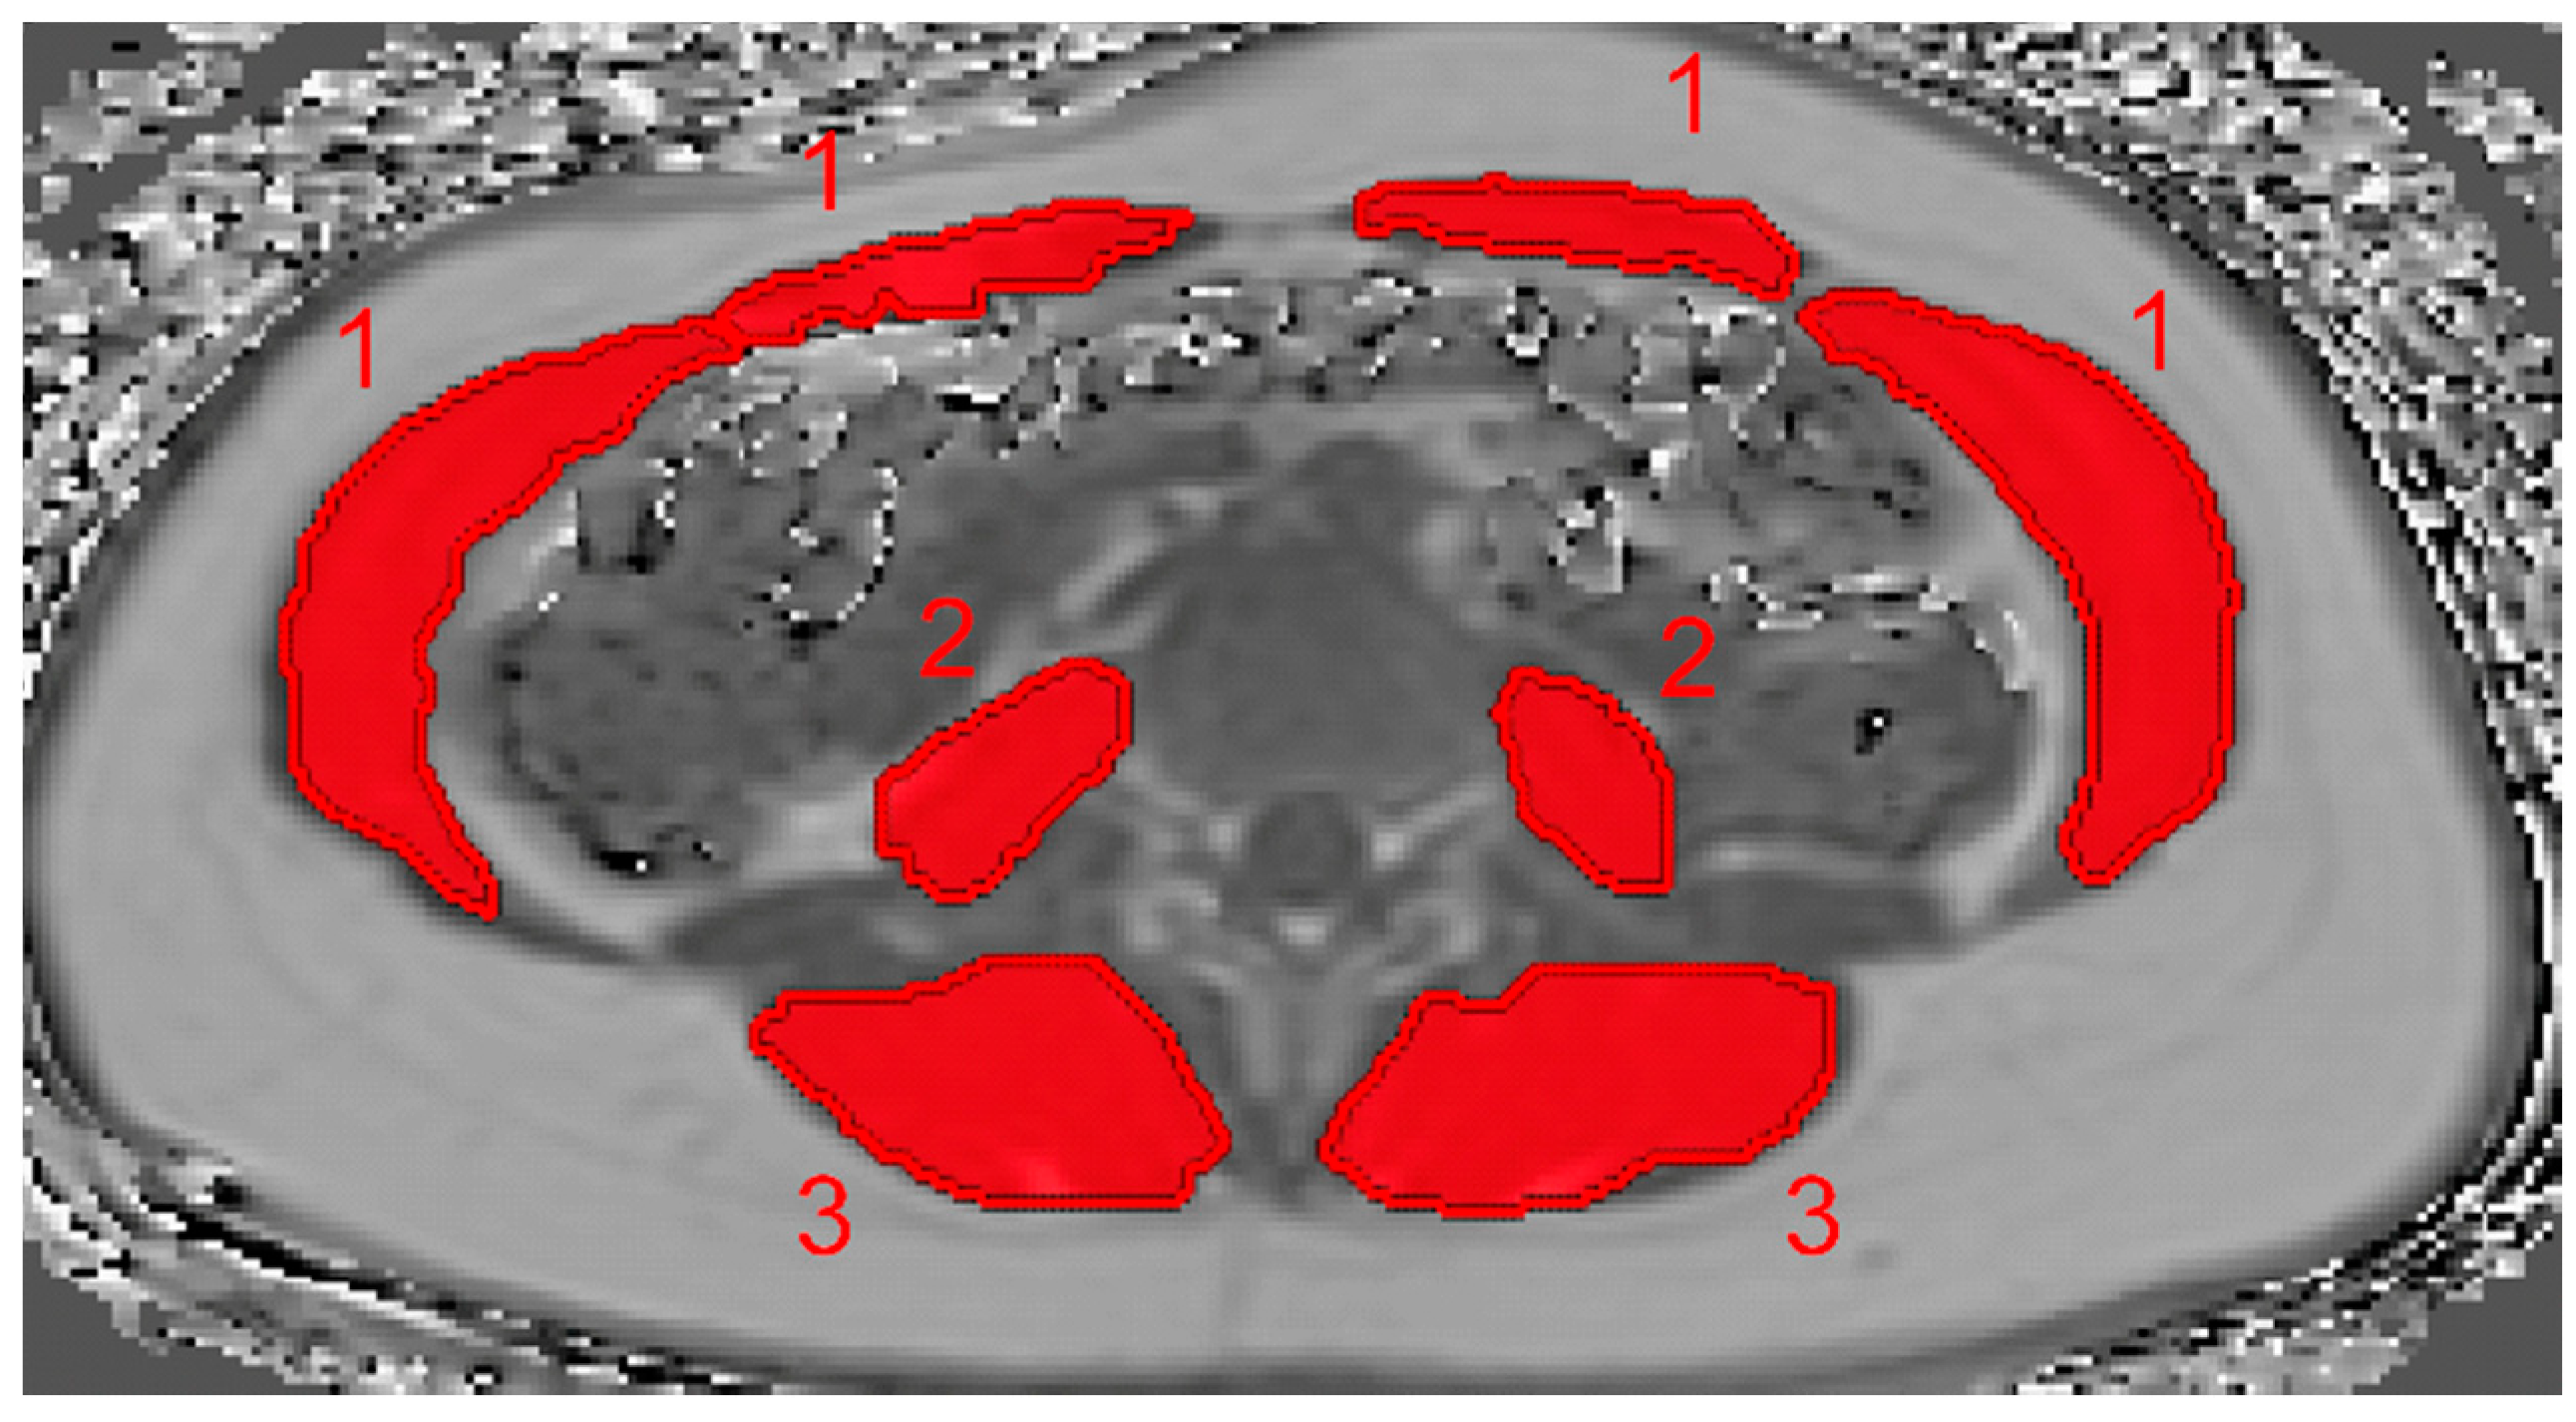

2.4. PDFF and CSA Calculation